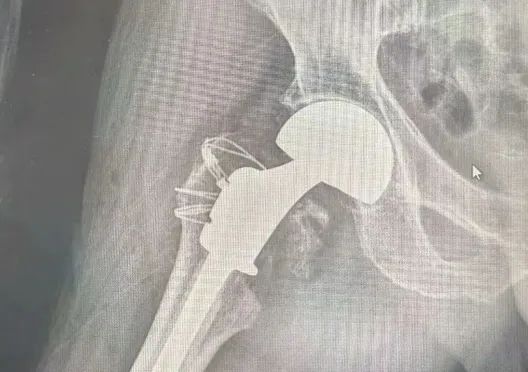

老一辈人都说,"伤筋动骨一百天",只有好好休息到3个月左右,才能慢慢恢复“元气”下地走路,然而这真的正确吗?"本以为我父亲年纪这么大,"右侧半髋关节置换"后至少也要在床上躺几个月,没想到做了手术第二天就能下床活动了!而且手术时间这么短就结束了!这太让人觉得惊讶了!"这是来自我院骨科患者92高龄爷爷家属的感叹,他们觉得这太不可思议了!

科室目前有员工45人,医师16人,护士24人,专业康复治疗师4人,宣教组1人,标准床位120张,科室现行开展机器人导航下行经皮椎弓根螺钉内固定术+植骨术,单髁置换术,反式全肩关节置换术,机器人辅助下膝关节置换术,髋关节置换术,脊柱内镜术,颈椎前后路开放术,腰椎后路TLIF术,骨肿瘤巨创术,肩、膝关节镜,股骨头坏死保髋术、腰椎椎体成形术,骨肿瘤切除+人工骨植入+钛板内固定术,颈椎前路微创术,双足距下关节关节制动术等。